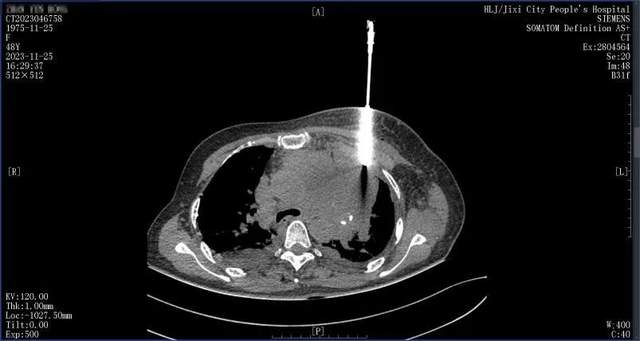

前港姐季军最新状况曝光!心肺积水留医半月,状态堪忧50岁的前港姐季军吴文忻(现名吴忻熹),在三年前不幸确诊患有乳癌。去年她的乳癌复发至第三期,癌细胞更是扩散至淋巴腺。 吴文忻积极投身于抗癌斗争中。她远赴泰国,尝试细胞免疫治疗,在一段时间内,治疗效果颇为理想,体内的癌细胞指数呈现出急剧下降的趋势。 然而,在2月24日,吴文...

吴文忻进入癌症末期,俩女儿哭着为妈妈剃头不舍亲吻此前半个月她又因心脏和肺部感染了积水住院治疗抢救,当时的吴文忻需要靠轮椅才可以进出,到医院里又是输血抢救又是打点滴,癌症恶化的情况非常不理想,但她仍旧坚持积极治疗,积极面对这一切。 近日她又透露自己发高烧,紧急入院之后又接受了一轮又一轮的治疗安排。吴文忻分享自...